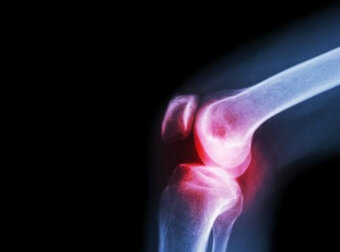

Die Symptome der septischen Arthritis variieren je nach Art der Infektion. Bei bakteriellen Infektionen ist meist nur ein Gelenk betroffen – typischerweise das Knie oder die Hüfte. In diesen Fällen ist jede Bewegung des betroffenen Gelenks sehr schmerzhaft. Diese Schmerzen sowie andere Symptome wie Fieber und Schüttelfrost entwickeln sich in der Regel schnell.

Anschließend könnten die Ärzte eine Röntgenuntersuchung des betroffenen Gelenks durchführen. Röntgenaufnahmen und andere bildgebende Diagnoseverfahren können bei der Einschätzung des Schadens helfen.